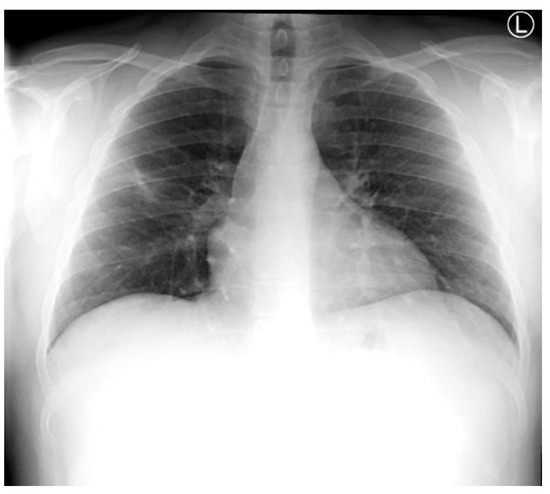

Introduction: Intravesical Bacillus Calmette-Guérin (BCG) instillation is the most effective adjuvant therapy for superficial urinary bladder carcinoma, prolonging disease-free survival. Although it is usually well tolerated, moderate to severe local or systemic infectious complications, including sepsis involving multiple organs, may occur. Case report: We report the unusual case of a man in his mid ‘70s who presented with septic shock and severe acute respiratory failure requiring intubation. Lack of response to antibiotics, history of intravesical BCG instillation and consistent imaging findings led to further investigations, with bronchoalveolar lavage (BAL) fluid polymerase chain reaction (PCR) results indicating pneumonitis due to Mycobacterium bovis dissemination. Prompt anti-tuberculosis treatment combined with corticosteroids resulted in significant clinical and radiological improvement, supporting the diagnosis of disseminated BCG infection. Conclusions: Due to its non-specific clinical presentation and the relatively low diagnostic yield of conventional microbiological tests, a high index of suspicion is required for prompt diagnosis and treatment of systemic BCG infection. PCR-based assays for mycobacterial DNA identification may represent a valuable tool facilitating timely diagnosis of this uncommon, yet potentially life-threatening infection. Full article

Show Figures

Figure 1